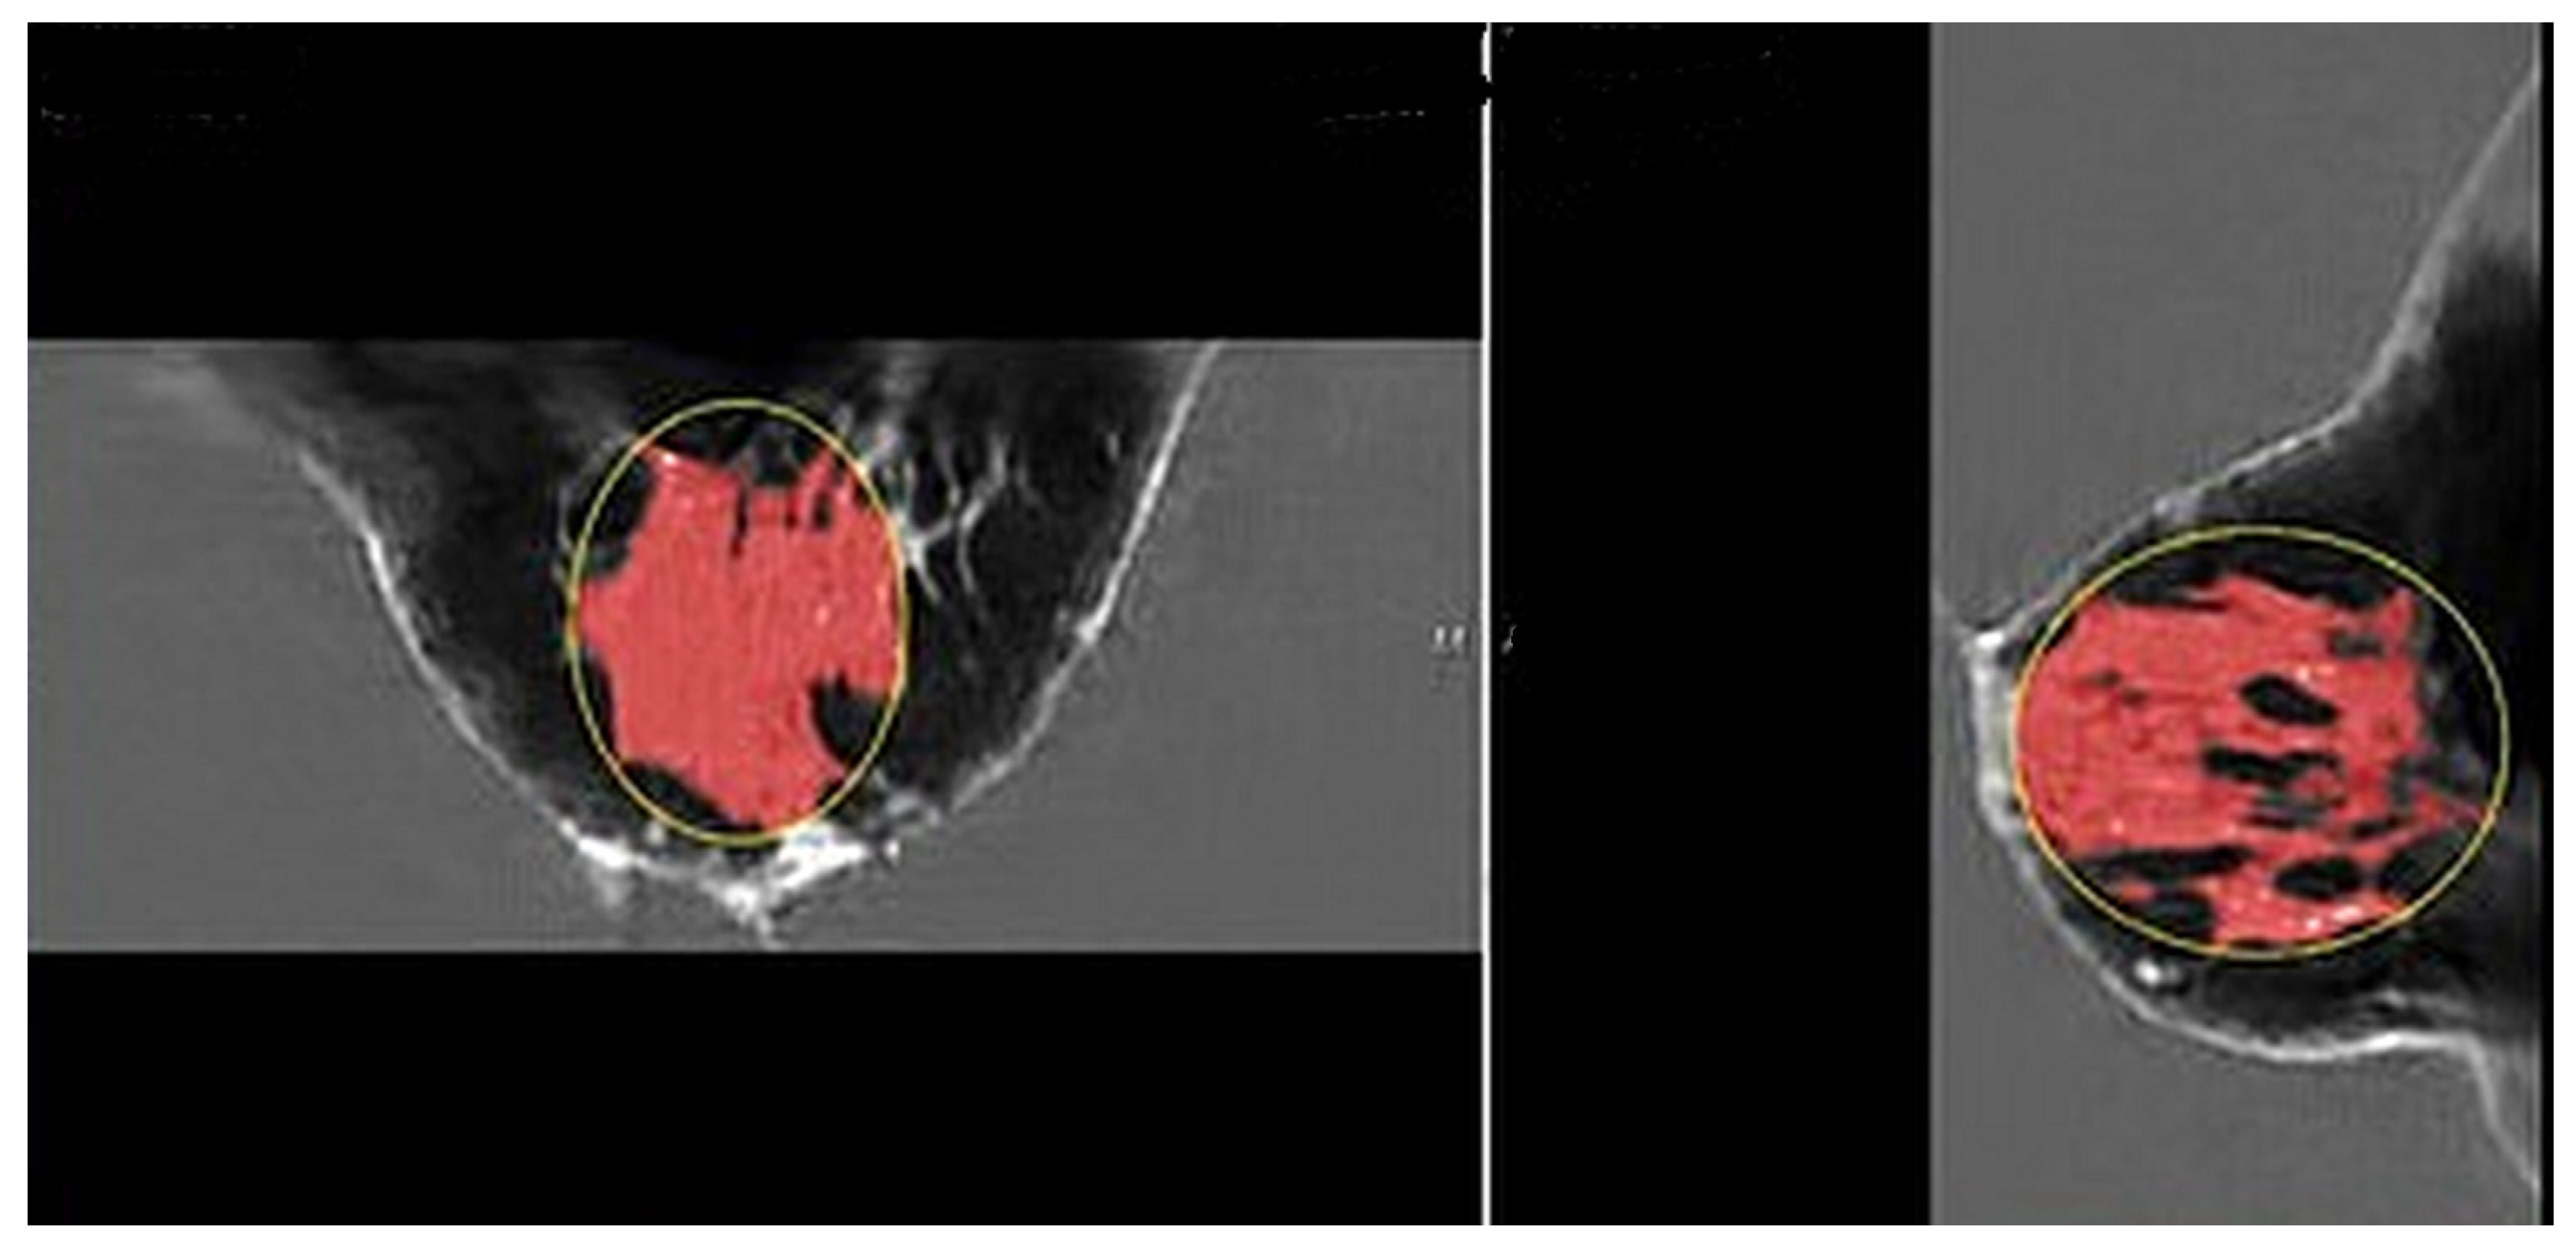

Figure 2 shows the speed of sound image of the entire FGV of a breast in axial (cranio-caudal) and sagittal (lateral) views. Figure 3 and Figure 4 show the glandular volume on day 1 of the menstrual cycle (Figure 3) and at the beginning of menstruation (Figure 4) in the same breast. These comparisons show increases in glandular volume at the onset of menstruation.

Figure 2. Pre-menstrual FGV in the axial (cranial-caudal; (left)) and sagittal (lateral; (right)) views. The red area is the segmented fibroglandular tissue. The yellow circle shows the initial constraining ellipsoid.